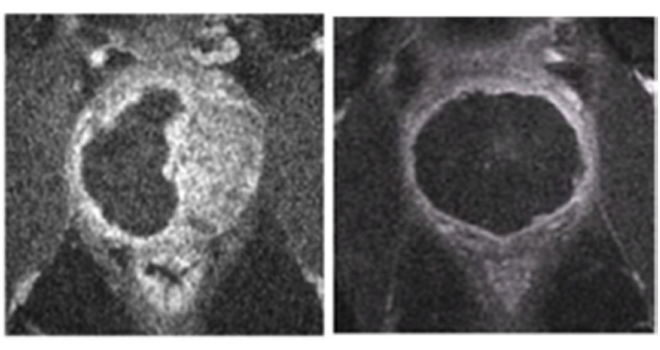

| Magnetic resonance images of a prostate gland, before (l) and after (r) treatment with Tookad Soluble and PDT. The central black regions in the right image show how cancerous tissue previously occluding the prostate have been eliminated. Image: Weizmann Institute of Science. |